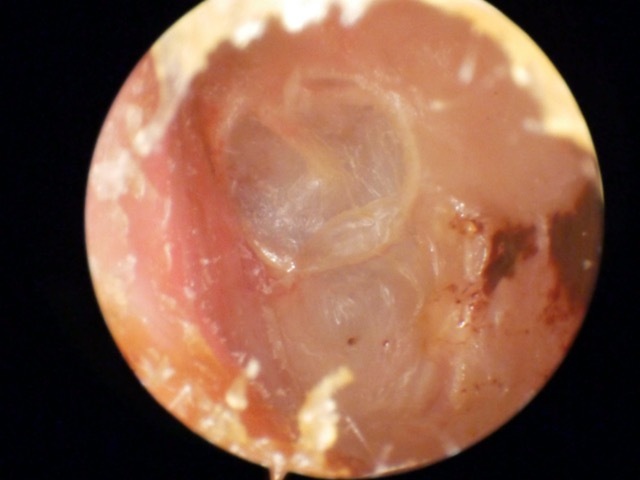

Atelectasis/Retraction

Ear Canal

Tympanic Membrane